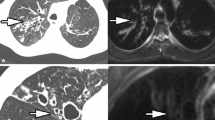

The basis for each score is the morphological, pathological alteration of the lung. These appear with different emphasis depending on the imaging modality: bronchial wall thickening, bronchiectasis, consolidations, bullae, mucus plugs and hyperinflation (Figs. 1, 2, 3, 4, 5 and 6) [16, 17]. In addition, functional assessment of regional changes in ventilation and perfusion is also desirable as complementary information.

A 16-year-old boy with cystic fibrosis. A T2 fast spin echo magnetic resonance (MR) image (a). The mucus in the bronchiectasis in the basal right upper lobe is hypointense on T2 (arrow). An axial unenhanced computed tomography (CT) image (b). The mucus in the bronchiectasis in the basal right upper lobe is hyperdense on CT (arrow). This combination of MR and CT findings is characteristic of allergic bronchopulmonary aspergillosis and aspergilloma

While T1 weighting is not mandatory for pulmonary MRI in most other conditions, it should be performed routinely in CF. The reason for this is the increased T1 signal in allergic bronchopulmonary aspergillosis, which along with the low T2 signal is considered characteristic of this disease (Fig. 5) [11]. Usually, T1 weighting is achieved as a 3-D gradient-echo acquisition in free breathing or during a single breath-hold command. Diffusion weighting may emerge as another parameter of disease severity in the future [43], but in routine diagnostics it is reserved for those situations when an abscess is suspected. Tables 1 and 2 provide exemplary protocols for different ages.